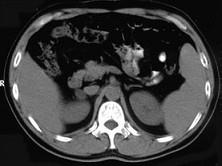

问题 女,23岁,满月脸、向心性肥胖,CT扫描如图所示,应诊断为()

选项 A.右侧肾上腺增生 B.右侧肾上腺腺瘤 C.右侧肾上腺腺癌 D.右侧肾上腺嗜铬细胞瘤 E.右侧肾上腺转移瘤

答案 B